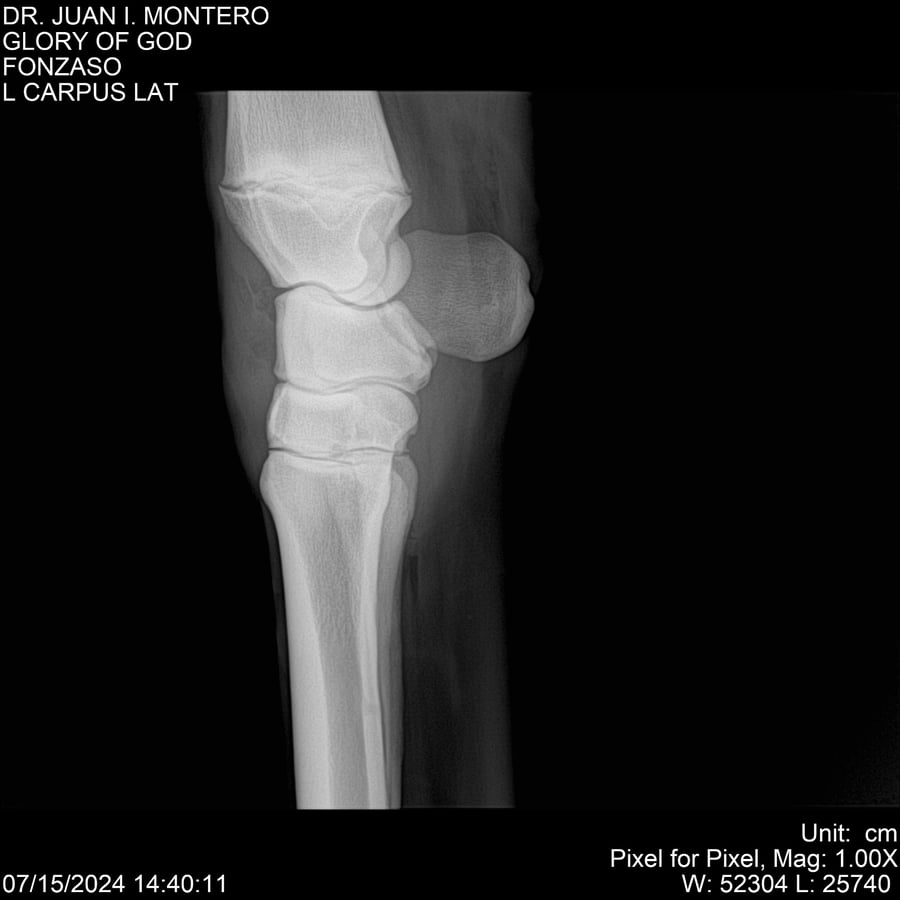

LOTE 10, GLORY OF GOD 🔥 🔥 🔥 Lote Anterior Volver al remate Lote Siguiente Ficha Contacto Montevideo - Ficha del Lote Identificador: #281389 Categoría: Yeguarizos Montevideo - 115 Visualizaciones ClicData Contacto Empresa: Abelenda N. R., Walter Hugo Nombre*: Teléfono* : E-mail* : Mensaje Enviar Registrese gratis Este contenido Exclusivo está disponible sólo para usuarios registrados Ingresar